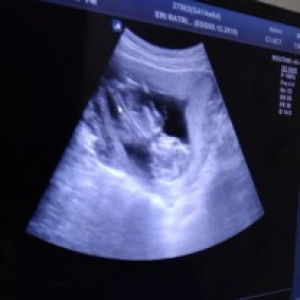

sharing yuk bund....bunda2 disini udah nambah brp size benahina nya (maaf bra mksdnya) dan udah usia brp kehamilannya??lagi galau nih...mau stok beli baru tp takut size nya nambah lagi...